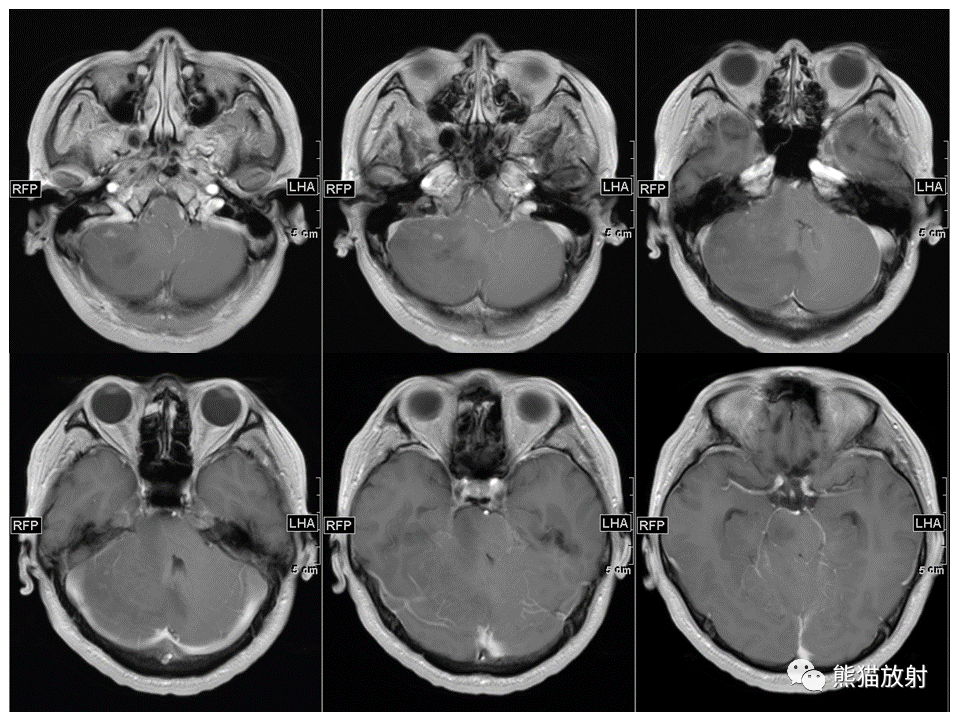

【PPT】小脑发育不良性神经节细胞瘤 VS 成人型髓母细胞瘤-4